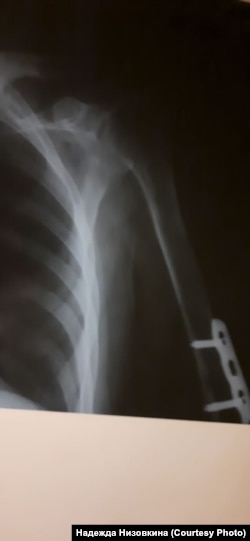

– Меня долгое время не пускали не то что в Советский отдел полиции, а даже во двор, все перекрыли! – возмущается адвокат Баирова Надежда Низовкина. – Подобное "задержание" и сокрытие человека – это, безусловно, преступление. Дмитрию же при этом еще и повредили руку – когда скрутили, задели штыри в руке, установленные после перелома, сейчас его мучают сильные боли. Потому что, найдя его через прокурора(!), мы добились, что его осмотрели медики, сделали снимки (медосвидетельствование показало повреждение мышечной ткани на месте сросшегося перелома), поставили обезболивающее, но продолжат ли его ставить – большой вопрос.

Опасения у адвоката вызывает и тот факт, что, несмотря на серьезность диагноза, на последней странице медзаключения (есть в распоряжении редакции) стоит отметка "содержание в ИВС не противопоказано".

– Учитывая, что такой запрос перед врачом не ставился, можно предположить, что он выполнял заказ, – рассуждает адвокат.